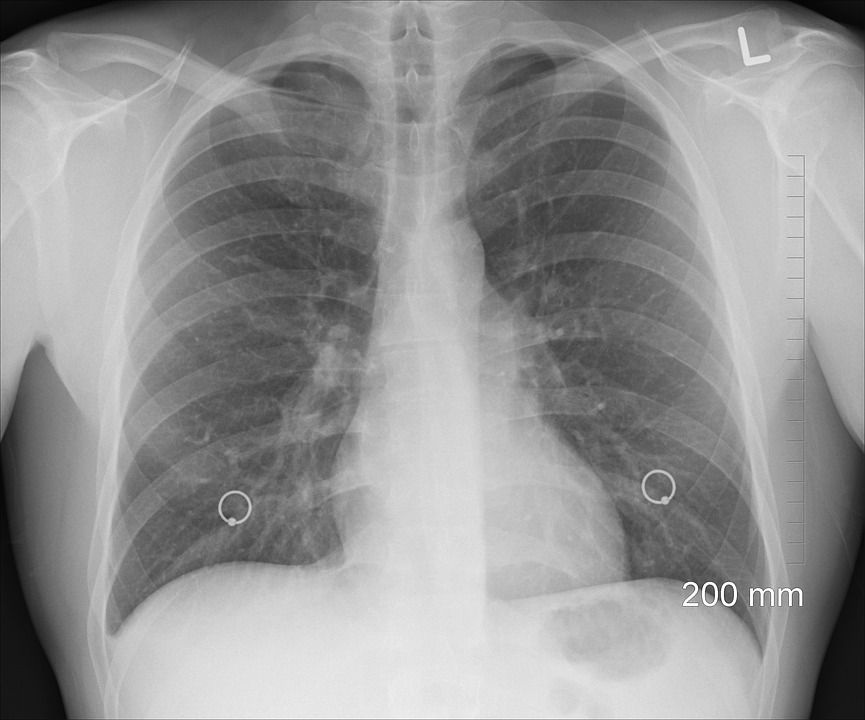

Podle SVL může být prvním zásadním krokem k modernizaci ordinací pořízení ultrazvuku a jeho využívání takzvanou metodou POCUS (point-of-care-ultrasound).

Tato ultrazvuková metoda pomůže na místě odhalit například zápal plic, žlučníkové kameny či žilní trombózu.

Úkolem je rychle zodpovědět specifickou diagnostickou, anebo terapeutickou otázku či usnadnit léčebnou proceduru: „Typickým příkladem je zápal plic.

Díky ultrazvuku, který provedu přímo v ordinaci, mohu rovnou nasadit léčbu nebo pacienta přesně a hned nasměrovat na další vyšetření. Tím se samozřejmě celkově zrychluje i jeho rekonvalescence,“ upřesňuje MUDr. David Halata.

Nyní sledujeme, jaká je přesnost vyšetření ve srovnání s ultrasonografisty například u vyšetření plic, žlučníkových kamenů nebo hluboké žilní trombózy dolních končetin.